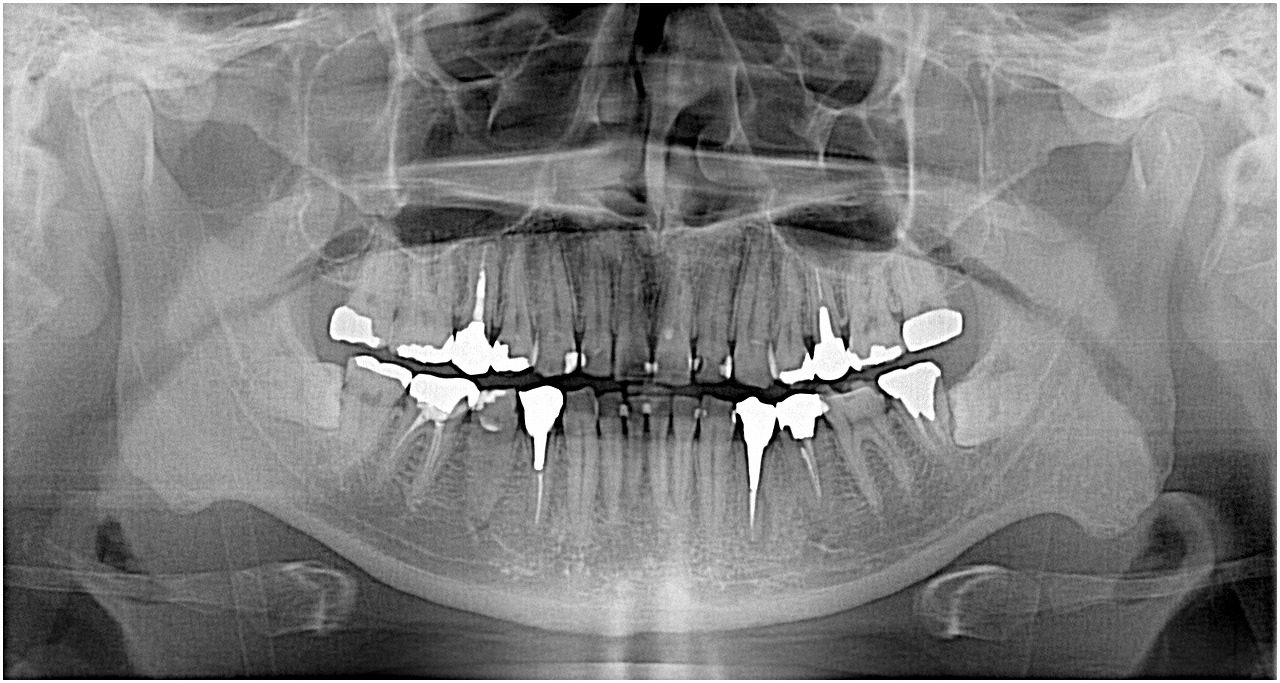

ブログ一覧|広島市安佐南区の歯科医院 ブログ一覧 トップ ブログ一覧 お知らせ スタッフブログ ブログ一覧 2017/11/16 埋入時のレントゲン。CTになります。 2017/11/16 右下のインプラント埋入。 2017/11/15 3カ月後には歯が入っています。 2017/11/15 埋入後から上部構造まで。 2017/11/15 左下4番の抜歯即時インプラント埋入。 2017/11/15 術後のデンタル。 10年前。 2017/11/15 右上最後臼歯の抜歯即時インプラント埋入。 最後臼歯は難しいです。 2017/11/15 術後レントゲン << 1 2 3 4 5 … 837 838 839 840 841 … 870 871 872 873 874 >> Web診療予約 初めての方へ 選ばれ続ける理由 院内設備について 歯が痛いしみる一般歯科 歯がぐらぐらする歯周病 健康な歯を保ちたい予防歯科 子供の虫歯予防をしたい小児歯科 銀歯をセラミックに審美歯科 白い歯を目指しませんか?ホワイトニング 矯正専門医がいるので安心矯正歯科 抜けた歯を補いたいインプラント・入れ歯 医院案内 スタッフ紹介 メリィハウス歯科クリニックオフィシャルホームページ ラベンダー歯科クリニックオフィシャルホームページ お知らせ・ブログ ホーム 診療科目 一般歯科 歯周病治療 予防治療 小児歯科 審美治療 ホワイトニング 矯正歯科 入れ歯・インプラント マウスピース矯正 初めての方へ 院長・スタッフ 設備紹介 医院案内・アクセス メニューを閉じる